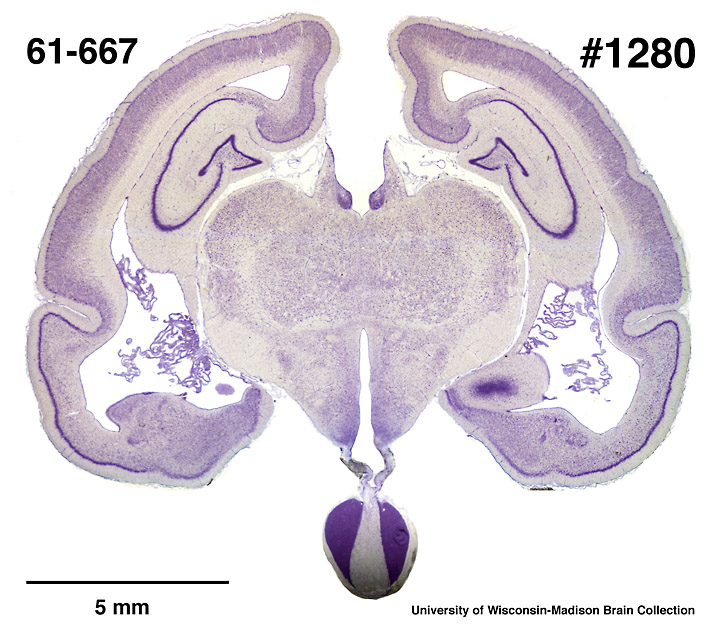

Coronal section through middle of brain .

Whole brain Photographs.